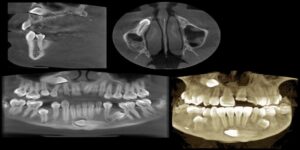

Planmeca CBCT Software Review: Romexis

Romexis is the 2D/3D all-in-one dental imaging software from the world-renowned dental imaging equipment manufacturer, Planmeca. As a solution for managing large 3D imaging files, Planmeca Romexis is one of the most powerful dental software platforms available on the market today. It offers a rich selection of tools and features for all needs and specialties. […]